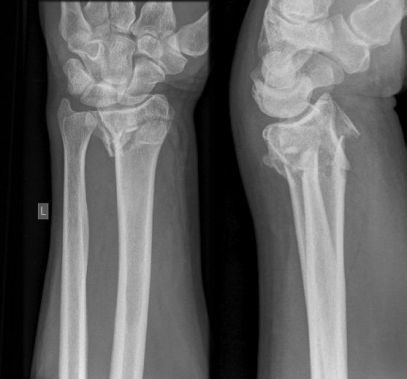

De breuk

Bij een polsbreuk is er een breuk van het spaakbeen, ellepijp of beide botten nabij de pols. Soms betreft het alleen een scheurtje in het bot, maar vaak is er verplaatsing van de botstukken. Behalve een letsel van het bot is er ook altijd kneuzing van de zogeheten weke delen, zoals pezen, spieren en eventueel vaten en zenuwen.

Indien er geen belangrijke verplaatsing van de botstukken is, dan wordt alleen een gipsspalk aangelegd. Indien de botstukken te veel verplaatst zijn, dan moet het bot worden “gezet” (teruggeplaatst). Dit gebeurt meestal onder plaatselijke verdoving door in het gebied van de breuk verdovingsvloeistof te spuiten. Deze verdoving werkt ongeveer een uur. Na het zetten van het bot wordt een gipsspalk aangelegd en wordt een röntgenfoto gemaakt om te controleren of de juiste stand is bereikt. Als een juiste stand niet wordt bereikt kan soms een operatie nodig zijn.

Operatie bij volwassenen

Indien er sprake is van een ernstige breuk met een slechte stand (ondanks zetten) of wanneer wordt ingeschat dat de stand van de breuk nog verder zal verslechteren, dan kan de traumachirurg samen met u bepalen dat er een indicatie is voor een operatie. Hiervoor zijn er meerdere opties. Het meest wordt er gebruik gemaakt van een plaatje en schroeven voor het vastzetten van de breuk. Soms wordt er ook gebruik gemaakt van stevige staaldraden of van een fixatie aan de buitenkant (zogenaamde ‘externe fixateur’).